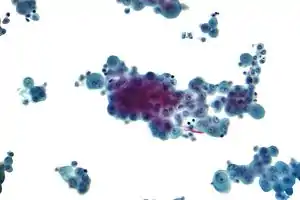

Micrograph of a pleural fluid cytopathology specimen showing mesothelioma.